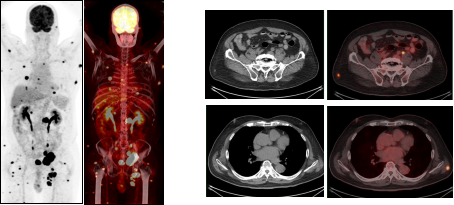

治疗前 治疗后

淋巴瘤治疗前后变化: 弥漫性大B细胞淋巴瘤化疗3程后,腹腔及腹膜后多发肿大淋巴结明显缩小,糖代谢明显减低。

(上两图为:治疗前,下两图为:治疗后)

淋巴瘤治疗前后变化:弥漫性大B细胞淋巴瘤化疗3程后,腹腔机腹膜后多发肿大淋巴结明显缩小,糖代谢明显减低。根据Deauville标准 5PS评分为2分。